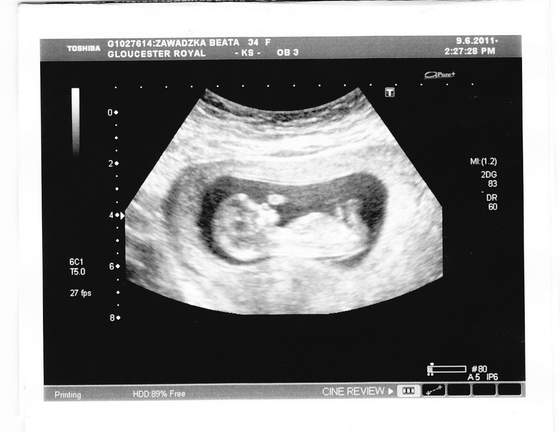

Nereida, żabcia, wprawdzie sama nie testowałam, ale, gdy kupowałam swój detektor, naczytałam się opinii temat tych kupowanych ze sklepów.Niestety, większość kobitek było rozczarowanych, niektóre pisały, że coś tam słychac ale dopiero w 30 tyg. Sama już kupiłam taki z firmy Lindam (bardzo podobne widziałam też z summer, angel sounds), po przeczytaniu tych opini odwołałam zakup. O wiele lepsze opinie mialy droższe wykrywacze z sondą/próbnikiem. Udało mi się wylicytować na aukcji taki z firmy

sonoline. Bicie serduszka znalazłam w 9 tyg, chociaż chwilę to trwało. Teraz w 12 znajduję bez problemu za każdym razem, bo już wiem, gdzie Dzidzi leży no i tez pewnie dlatego, że urosła. I przyznam się, że przy pierwszych próbach, gdy jeszcze nie było słychać (8 tydz.) też miałam wkręty, że coś może być nie tak z Małą. Niepotrzebny stres.